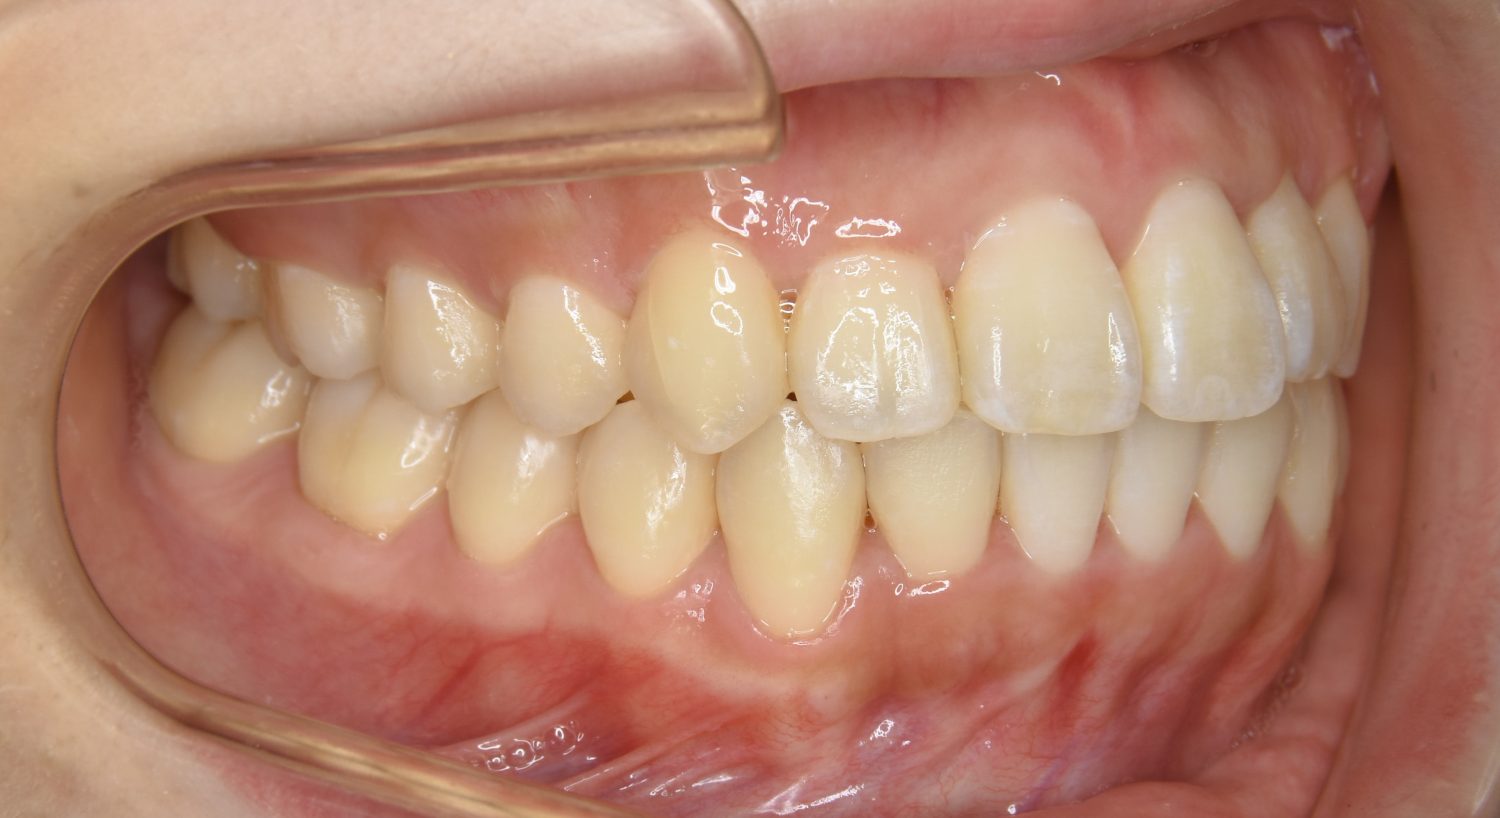

叢生の症例紹介②

Before

After

主訴

歯の凸凹を治したい。

治療内容

アライナー(インビザライン)にて非抜歯で治療を行いました。

上下前歯部に叢生(凸凹)が認められる状態でした。歯列の遠心移動を行うことで機能面および審美面が改善されました。